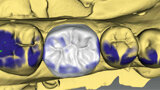

Figs. 3a & 3b. Diseño de la corona con el software (inLab) y prueba de la corona antes de la cocción de cristalización (IPS e.max CAD).